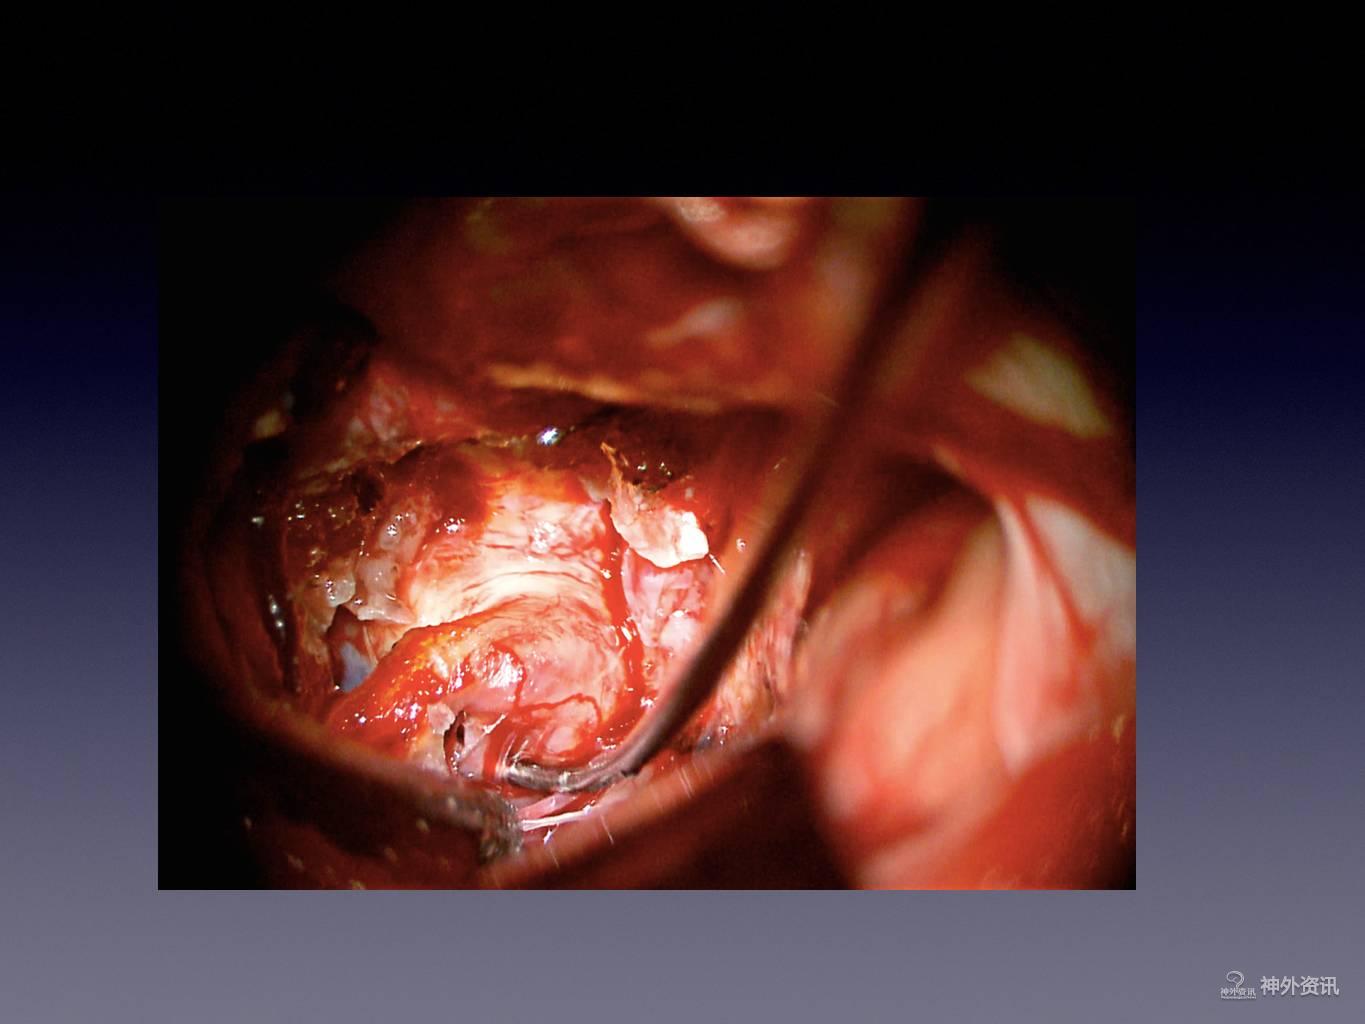

王林教授:床突旁动脉瘤夹闭手术

今天为大家分享的是《正海-妙术视界》第二十二期,由浙江大学医学院附属第二医院神经外科王林教授带来的床突旁动脉瘤夹闭手术,视频非常精彩,欢迎观看。